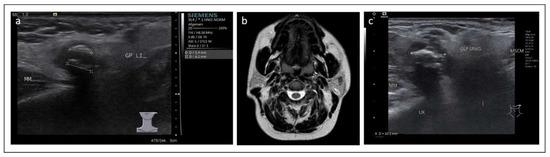

2. Case 1

3. Case 2